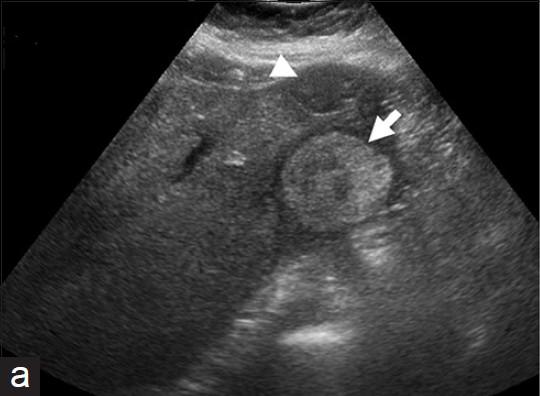

What is the sonographic appearance of Polycystic liver disease?

Anechoic

Thin well-defined walls

Posterior

enhancement

Multiple

Varying in small size